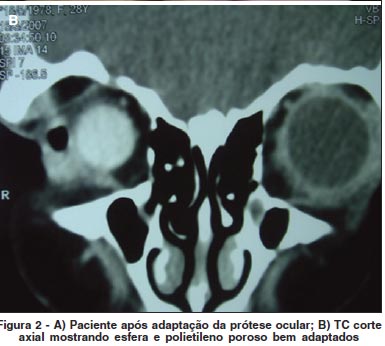

Obtivemos um bom resultado cosmético, de mobilidade e de volume após adaptação da prótese escleral (Figura 2A).

A tomografia computadorizada realizada após 6 meses da cirurgia mostrou implante bem posicionado na órbita, não apresentando nenhum sinal de infecção, migração ou extrusão do implante (Figura 2B).